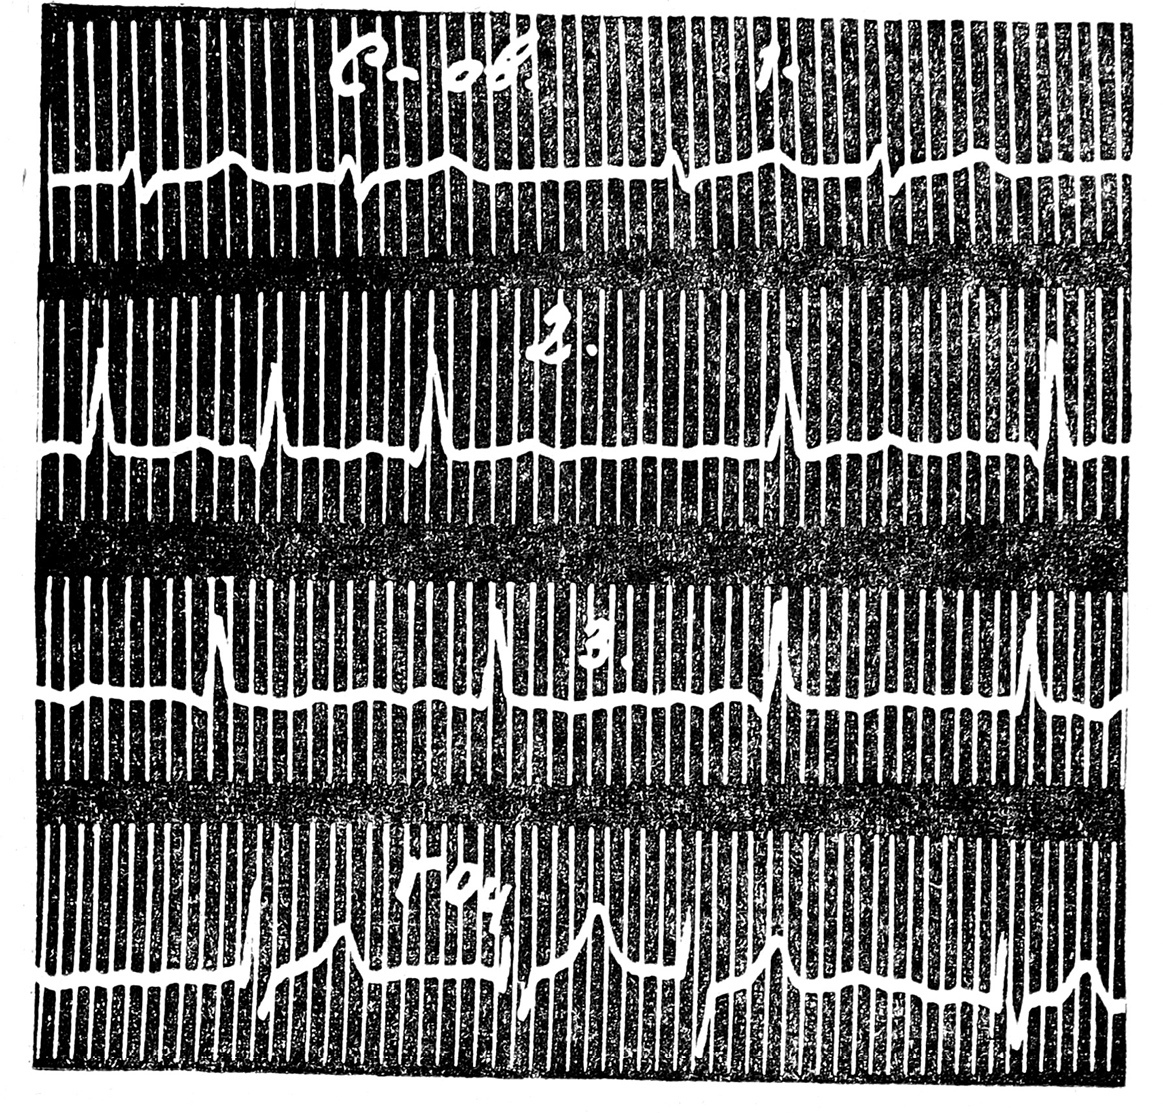

На ЭКГ, снятой вне приступа, патологических отклонений не выявлено. Во время приступа мерцательной аритмии (24/XII-58 г., см. рис. 1) отмечено крупноволновое мерцание предсердий с частотой желудочковых сокращений от 60 до 133, небольшое замедление внутрижелудочковой проводимости (QRS = O,11).

Рис. 1. ЭК Г больного С. от 24/XII-58 г